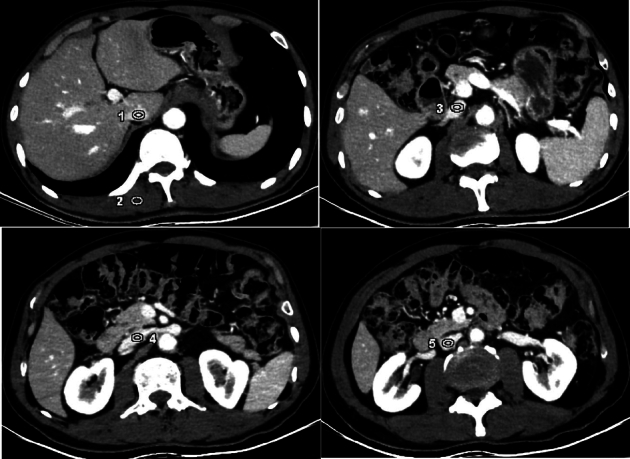

Results: The objective CT value, SD, SNR, and CNR increased with the decrease in energy level, with statistically significant differences (all P <0.05). The 40 keV images had the highest CT values, SNR, and CNR and good diagnostic acceptability, and 40 keV was selected as the best energy level. Compared with ASiR-V40% and DLIR-M, DLIR-H had the lowest SD, highest SNR and CNR, and subjective score (all P <0.001) with good consistencies between the 2 physicians (all k ≥0.75). The 40 keV images with DLIR-H had the highest overall image quality, showing sharper edges of inferior vena cava vessels and clearer lumen in patients with Budd-Chiari syndrome.

Conclusions: Compared with the ASiR-V algorithm, DLIR-H significantly reduces image noise and provides the highest CNR and best diagnostic image quality for the 40 keV DEsCT images in imaging inferior vena cava.